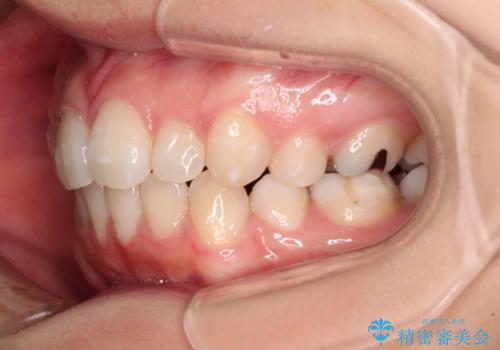

- 下顎前歯を中心に、以前行った矯正治療の後戻りが気になるとのことで来院された患者様です。

後戻りは軽度であったため、インビザライン・ライトにて治療を行うこととしました。